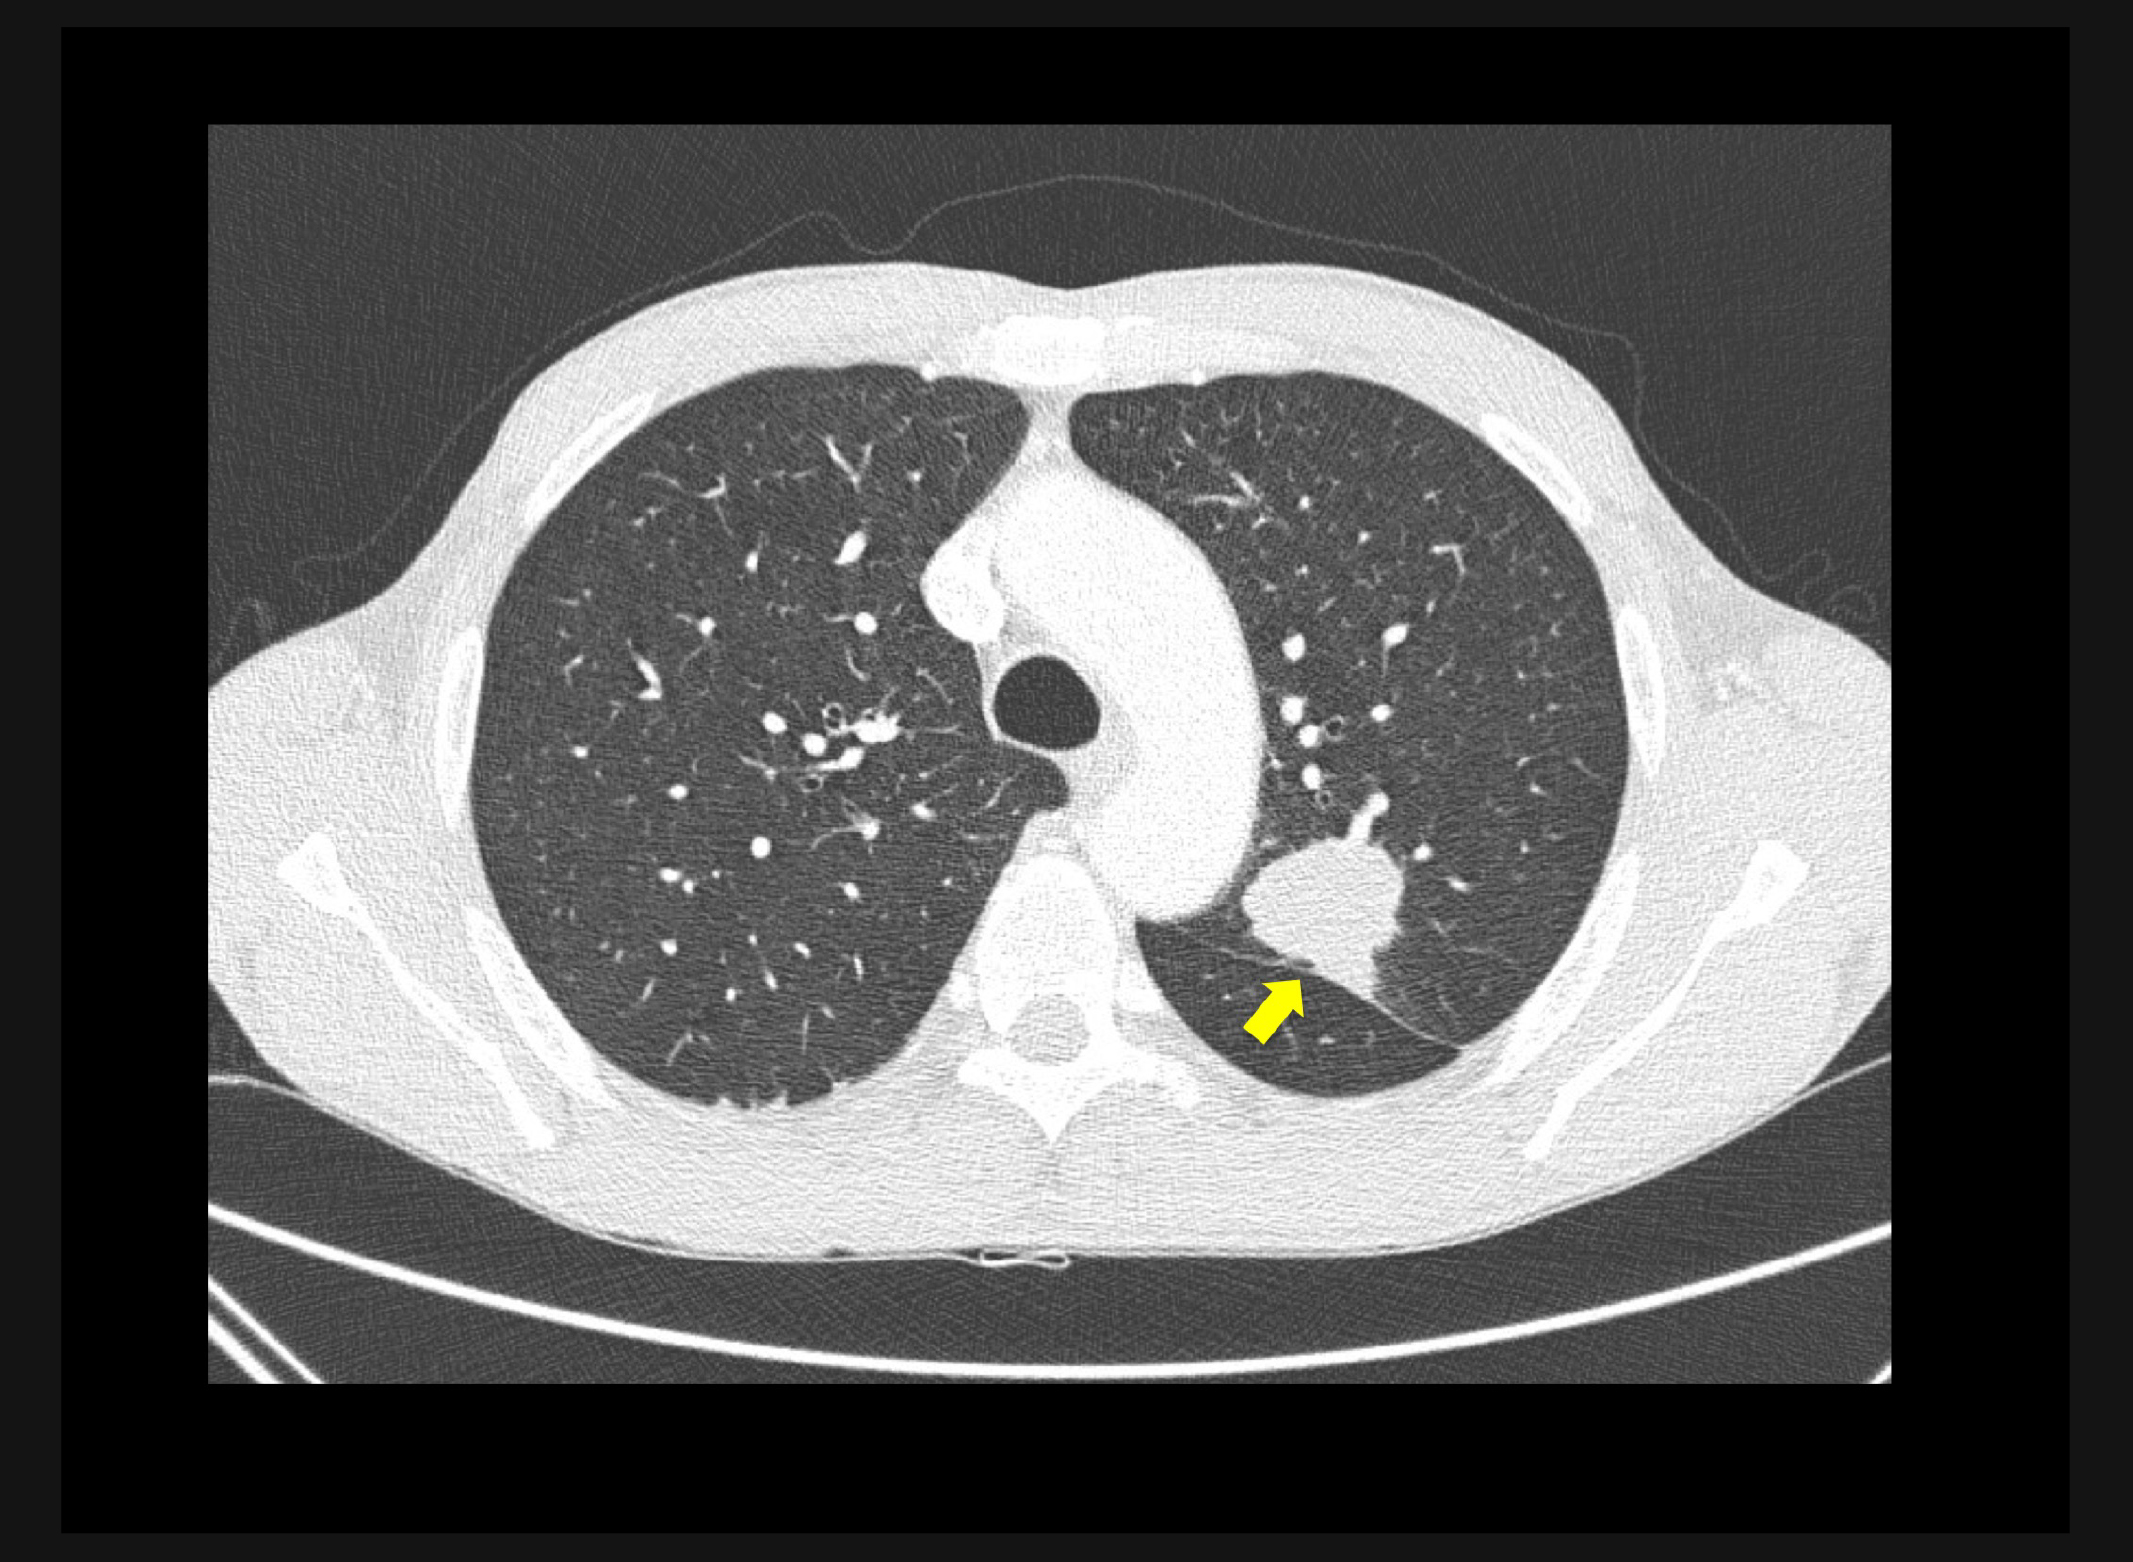

Se realizó una punción biopsia y el paciente fue diagnosticado de adenocarcinoma de pulmón. Como exploraciones adicionales se realizó una broncoscopia para intentar biopsia de posibles adenopatías pero como complicación del procedimiento, se produjo una perforación traqueal, por lo que el paciente fue sometido a una linfadenectomía mediastínica videoasistida. En TC de control posterior se observa la presencia de la perforación de la pared anterior de la tráquea a nivel de la carina con importante neumomediastino y enfisema de partes blandas cervico-torácico (Figura 3). Se aprecian en la TC imágenes de tromboembolismo pulmonar (TEP) bilateral de alta carga trombótica.